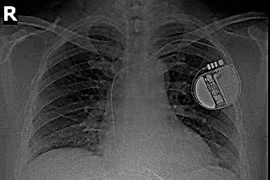

Một bệnh nhân 41 tuổi thoát khỏi đột tử nhờ cấy máy phá rung tim sau khi gặp rối loạn nhịp nguy hiểm, nhấn mạnh tầm quan trọng của khám sức khỏe định kỳ.